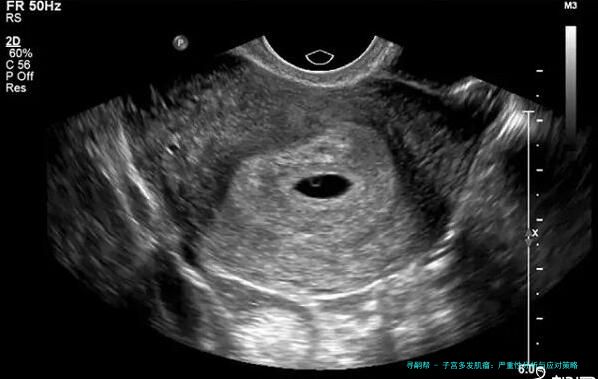

子宫多发肌瘤:严重性分析与应对策略

首先,子宫多发肌瘤简单来说,就是子宫里长了不止一个肌瘤。这些肌瘤是良性的肿瘤,由平滑肌和结缔组织组成,通常不会癌变。症状因人而异,有的人可能完全没感觉,而有的人则会经历月经量增多、腹痛、腰酸背痛,甚至影响排尿或生育。举个例子,我认识的一位阿姨,她就是因为月经期太长、量太大,才去医院检查,结果发现是多发肌瘤。医生说,这病在中年女性中更常见,但近年来年轻女性发病率也有上升趋势,可能跟生活压力大、饮食不规律有关。